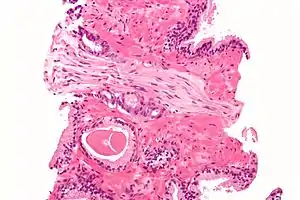

Within a nerve, each axon is surrounded by a layer of connective tissue called the endoneurium. The axons are bundled together into groups called fascicles, and each fascicle is wrapped in a layer of connective tissue called the perineurium. Finally, the entire nerve is wrapped in a layer of connective tissue called the epineurium. Nerve cells (often called neurons) are further classified as sensory, motor, or mixed nerves.

Structure

Each nerve is covered on the outside by a dense sheath of connective tissue, the epineurium. Beneath this is a layer of fat cells, the perineurium, which forms a complete sleeve around a bundle of axons. Perineurial septae extend into the nerve and subdivide it into several bundles of fibres. Surrounding each such fibre is the endoneurium. This forms an unbroken tube from the surface of the spinal cord to the level where the axon synapses with its muscle fibres, or ends in sensory receptors. The endoneurium consists of an inner sleeve of material called the glycocalyx and an outer, delicate, meshwork of collagen fibres.[2] Nerves are bundled and often travel along with blood vessels, since the neurons of a nerve have fairly high energy requirements.